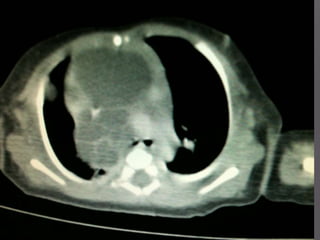

 Malignant germ-cell tumour in a 25 year old man presenting with chest

pain, dyspnoea, malaise and features of pericardial tamponade. The CT

shows a lobular asymmetrical mass with low attenuation areas

corresponding to necrotic tumour intersected by neoplastic septation.